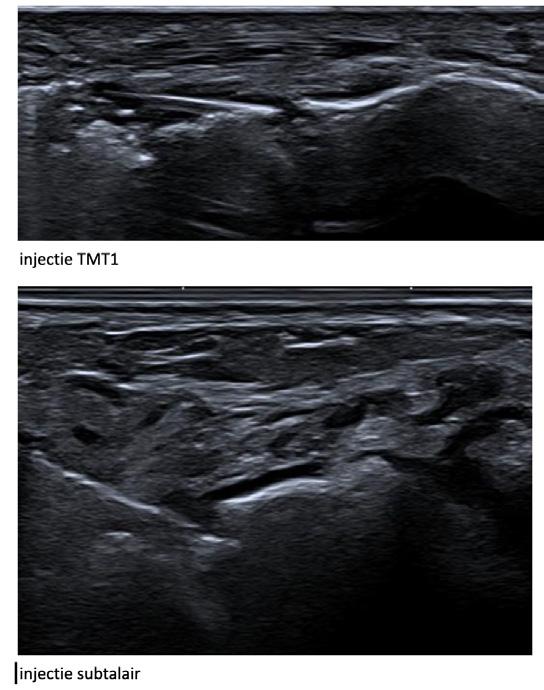

2. Therapie resistente tendinopathiën al dan niet met fissuren of partiële scheur

Studies tonen aan dat PRP de functionele activiteit verbetert en pijn vermindert. De injectie gebeurt onder echogeleide, strikt steriel, in de pees en eventueel in de peesschede. De hoeveelheid wordt aangepast aan de grootte van het letsel en zonder uitoefenen van overmatige druk.

Borne J, Ponsot A, Bordet B et al., Nouvelles indications d’injection de PRP autologue sous echographie dans la pathologie du pied et de la cheville. Actualités en échographiecde l’appareil locomoteut Vol. 19 ,129-141, 2024 (Sauramps medical)

Sconfienza LM, Adriaensen M, Albano D. Clinical indications for image guided interventional procedures in the musculoskeletal system: a delphi based consensus paper from the European Society of Musculoskeletal Radiology Eur Radiol. 2022;32(2):1384-94

Tenniselleboog injectie

Rotator cuff injectie

Injectie in achillespees

Verspreiding van het PRP in de tendinopathie